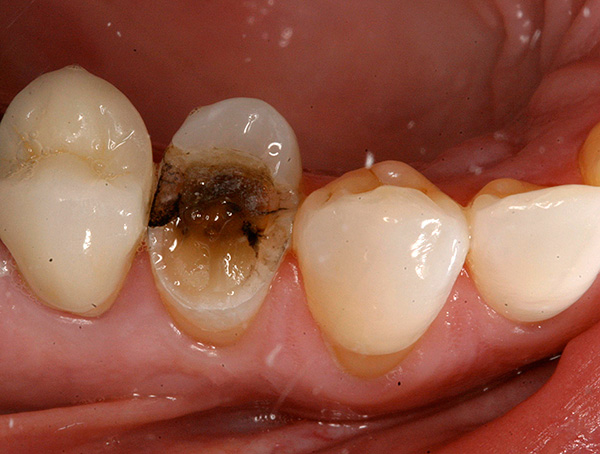

- Se la corona del dente è quasi completamente distrutta, allora stiamo parlando della rimozione della radice;

La foto sotto mostra la radice del dente rotto da rimuovere:

Come avviene l'estrazione di denti gravemente danneggiati e quanto costerà?

Molte persone che si trovano di fronte alla necessità di rimuovere un dente gravemente danneggiato sono preoccupate per un momento del genere: un chirurgo dentista sarà in grado di afferrarlo con una pinza, perché in realtà non c'è nulla da afferrare.

Vediamo come appare dal punto di vista di un medico.

In pratica, molto spesso è impossibile dire in anticipo con certezza al 100% se la rimozione è semplice o complessa. Tuttavia, ci sono alcuni "suggerimenti" per il dentista che suggeriscono se ci si può aspettare una rimozione complessa o meno. Ad esempio, è più difficile rimuovere un dente in presenza dei seguenti fattori: